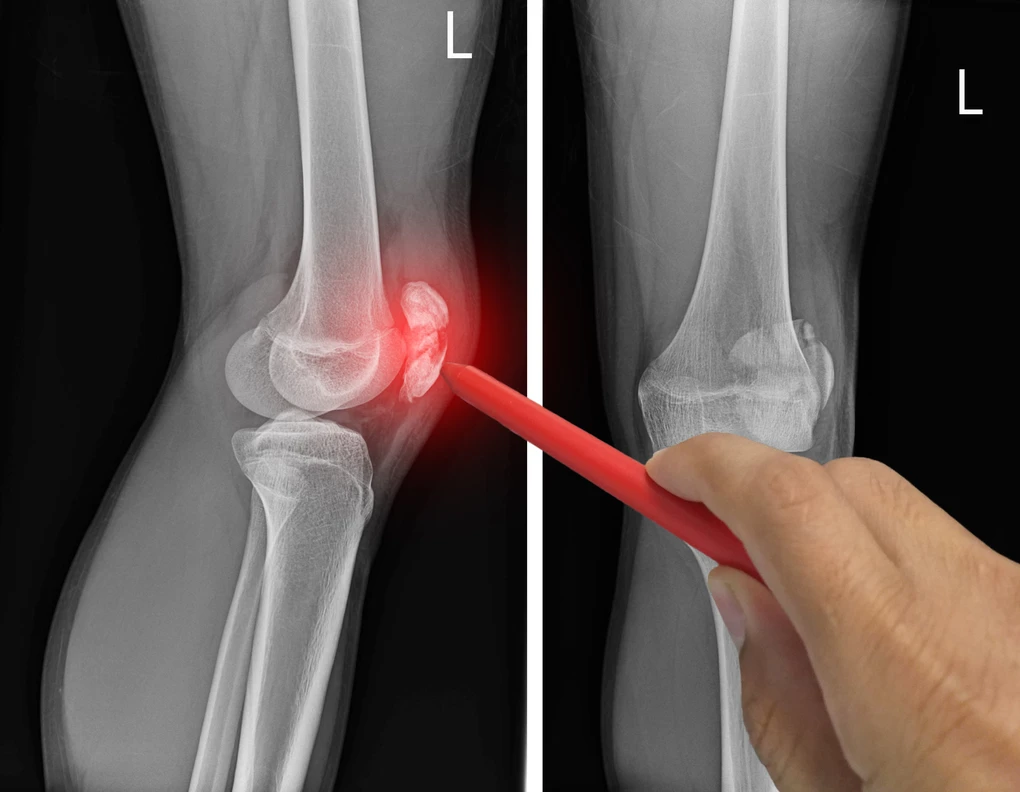

Comprehensive Guide to Patella Fractures (Kneecap Fractures)

A patella fracture, commonly referred to as a kneecap fracture, is a serious injury that can significantly impair knee function and mobility. As a crucial component... read more